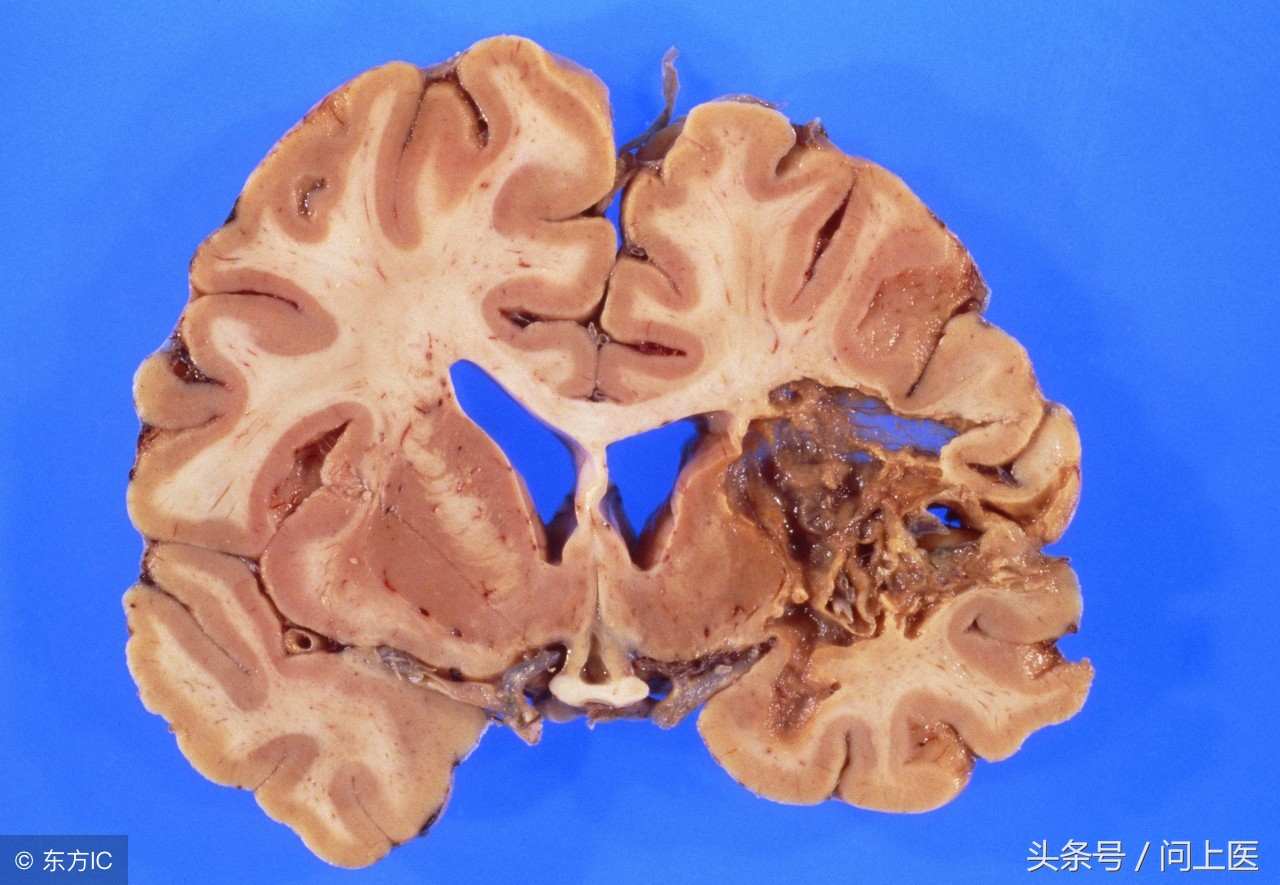

• 脑出血性中风

多发生在脑血管破裂或被破坏时。其结果是血液渗入脑组织,对脑细胞造成损害。而出血性脑中风最常见的原因是血压高和脑动脉瘤。动脉瘤常存活于血管内壁,质地比较薄弱。出血性中风的死亡率更高,但是幸存者完全康复的可能性也较高。

1.脑疝

脑血管病患者多数死于急性期,其原因大多是由于大量出血,脑中线结构移位或被破坏,全脑水肿,形成脑疝,使脑干被挤压和移位,危及生命中枢所致。

国内报道,脑出血合并脑疝死亡者占44.8%~50.1%,故及时有效地降低颅内压,减轻脑水肿,预防脑疝形成,是治疗成败的关键措施。而当患者出现下列情况:①头痛剧烈或极度烦躁不安;②频繁呕吐或抽搐;③呼吸及心率变慢,血压升高;④意识障碍逐渐加重;⑤双侧瞳孔不等大,则提示颅内压明显增高,可能有脑疝形成,应积极脱水或手术治疗。